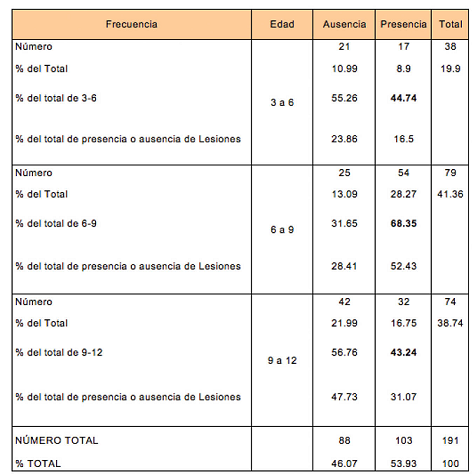

Los datos fueron también analizados por grupos de edad. Se agruparon los sujetos de acuerdo a los grupos de edad: 3-6 años ( 3 ≤ edad < 6) , 6-9 años (6 ≤ edad < 9), y 9-12 años (9 ≤ edad ≤12).

Se observaron diferencias significativas entre la proporción de lesiones en los distintos grupos etarios. El 68,35% de los sujetos en el grupo de 6-9 presentó lesiones, mientras que la proporción fue significativamente menor para los grupos de 3-6 (44,74%) y de 9-12 (43,24%) (valor-p = 0.0033**) (Tabla 3).

Se encontraron diferencias significativas (valor-p = 0.0048**) entre la prevalencia de Morsicatio buccarum en los tres grupos de edad, mostrando mayor incidencia en el grupo de 6-9 años (62%), seguido por el grupo de 3-6 (42%), y por último el de 9-12

años (36%) (Tabla 4).